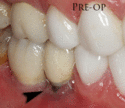

The gingiva surrounding a tooth has a 2–3 mm band of bright pink, very strong attached mucosa, then a darker, larger area of unattached mucosa that folds into the cheeks. When replacing a tooth with an implant, a band of strong, attached gingiva is needed to keep the implant healthy in the long-term. This is especially important with implants because the blood supply is more precarious in the gingiva surrounding an implant, and is theoretically more susceptible to injury because of a longer attachment to the implant than on a tooth (a longer biologic width).[28](pp629–633)

When an adequate band of attached tissue is absent, it can be recreated with a soft tissue graft. There are four methods that can be used to transplant soft tissue. A roll of tissue adjacent to an implant (referred to as a palatal roll) can be moved towards the lip (buccal), gingiva from the palate can be transplanted, deeper connective tissue from the palate can be tranplanted or, when a larger piece of tissue is needed, a finger of tissue based on a blood vessel in the palate (called a vascularized interpositional periosteal-connective tissue (VIP-CT) flap) can be repositioned to the area.[25](pp113–188)

Additionally, for an implant to look esthetic, a band of full, plump gingiva is needed to fill in the space on either side of implant. The most common soft tissue complication is called a black-triangle, where the papilla (the small triangular piece of tissue between two teeth) shrinks back and leaves a triangular void between the implant and the adjacent teeth. Dentists can only expect 2–4 mm of papilla height over the underlying bone. A black triangle can be expected if the distance between where the teeth touch and bone is any greater.[18](pp81–84)